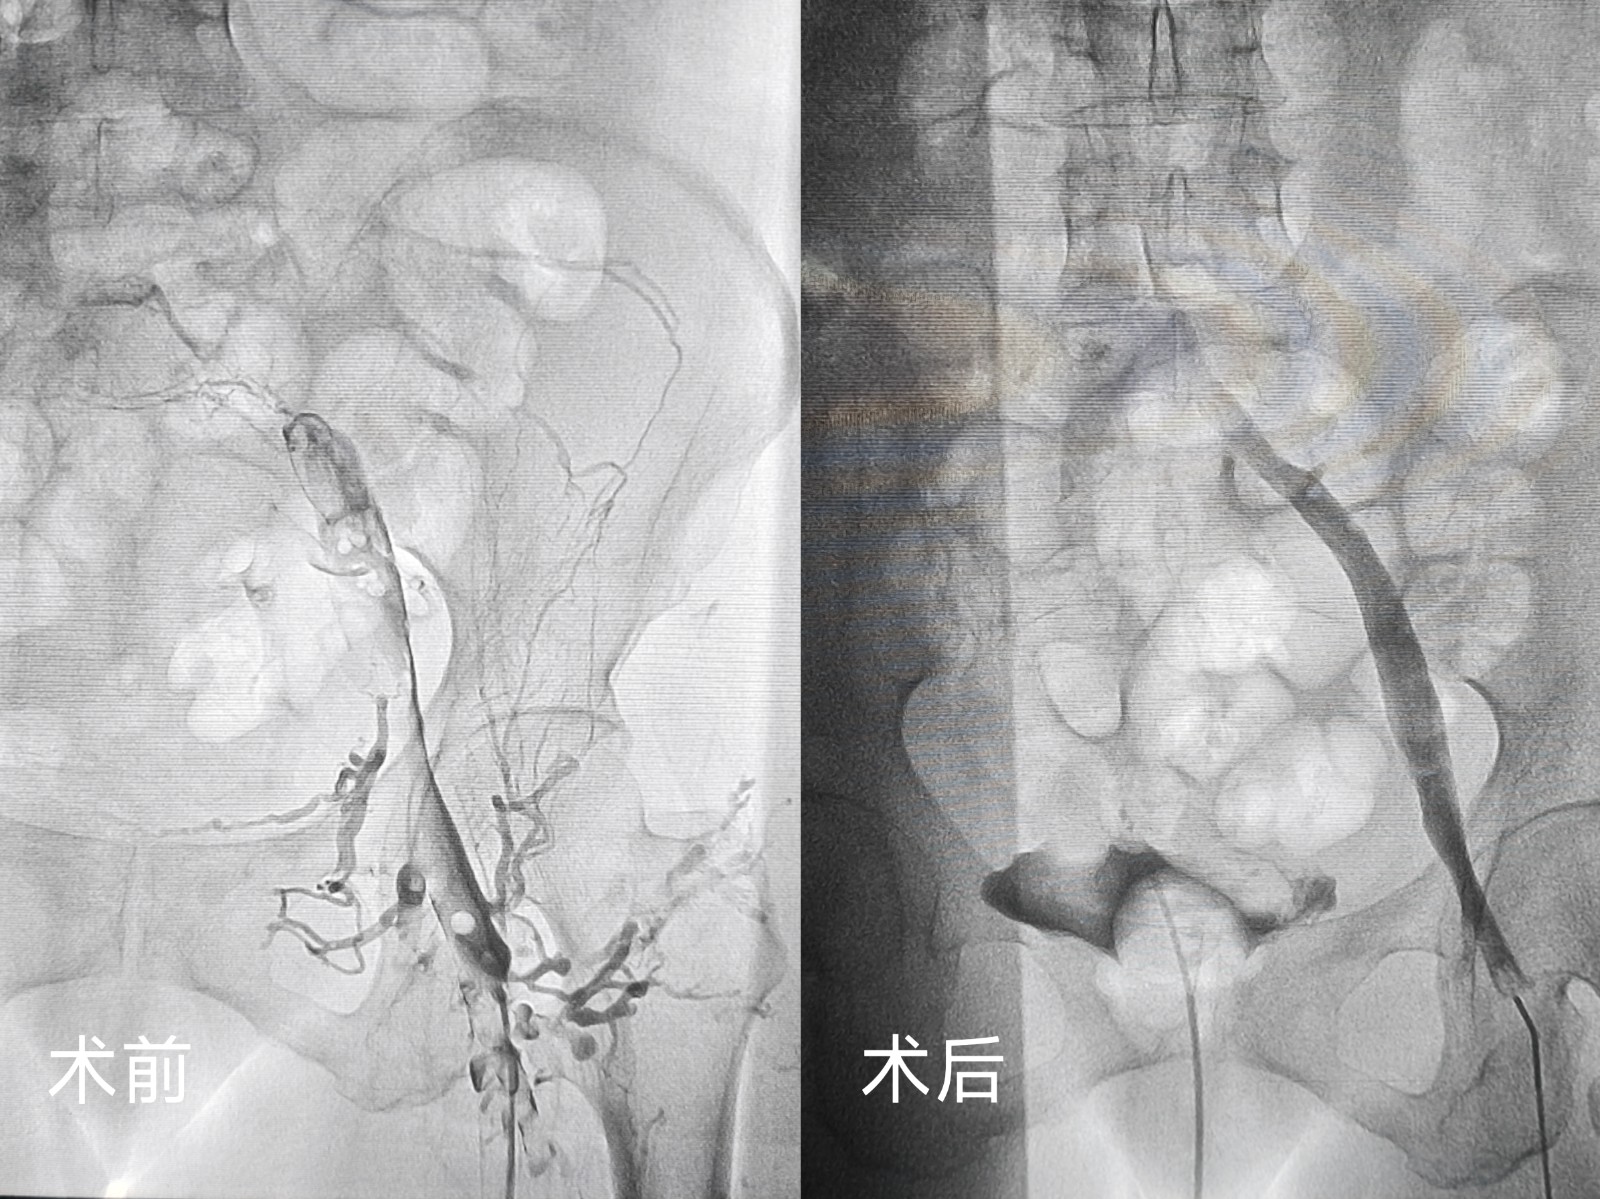

鄂西北首例应用患者因外伤导致双下肢深静脉血栓,转入十堰市人民医院心胸大血管外科时已在外院接受滤器置入术。患者外伤术后同时合并贫血,病情复杂且风险较高。传统的治疗方案失血量较高,科室医疗团队结合患者具体情况,制定了个性化治疗方案,决定采用外周静脉取栓支架系统实施下腔静脉及下肢静脉取栓术。手术过程中,团队发现此前置入的滤器内已形成血栓,为避免血栓脱落风险,当即调整手术方案,在精准置入新滤器后,成功回收旧滤器,同时利用外周静脉取栓支架系统高效清除静脉内阻塞血栓。

无独有偶,一位左下肢突发肿胀伴剧烈疼痛的患者,在症状出现仅1天后便慕名前来求医。患者病情进展迅速,肢体肿胀明显,疼痛难忍,严重影响正常行走。科室团队快速响应,经详细检查后明确诊断为左下肢深静脉血栓,随即为患者安排紧急手术。术中,团队先为患者置入滤器预防肺栓塞,再运用同款外周静脉取栓支架系统,精准、高效地清除了下肢静脉内的血栓。

外周静脉取栓支架系统作为一种纯机械取栓装置,无需溶栓药,完全避免了溶栓药物相关的出血风险,减少药物喷洒对血管的刺激,在临床治疗中展现出独特优势。相较于传统治疗方式,其能大大减少术中失血量,更安全、快速、彻底地清除静脉内血栓。除急性外还能用于亚急性甚至慢性血栓,降低血栓残留、复发以及远期血栓后综合征(PTS)的发生风险,同时减少手术对患者的创伤,加速术后康复进程。